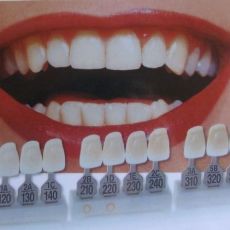

Puneți coroana pe dintele din față. Din fericire, este destul de ușor să remediați această deficiență - puteți pune coroana pe dinte. Rețineți că coroanele metalice, care au atins vârful popularității cu aproximativ 20 de ani în urmă, nimeni nu vă va oferi nici măcar. Cele mai populare acum folosesc cermet coroane dentare, prețurile pentru care sunt disponibile pentru majoritatea. Puteți pune o coroană pe dinte, prețul căruia depinde foarte mult de nivelul clinicii și puteți face chiar și un pod metal-ceramic în absența mai multor dinți la rând. Necesitatea de a instala o coroană pe dinte și alegerea ei ar trebui decisă numai împreună cu medicul la o recepție personală. Desigur, coroanele dinților din față sunt cel mai bine realizate din ceramică, fără metal. Acest dezavantaj estetic al cermetelor pe dinți, ale căror prețuri sunt destul de accesibile, se explică prin faptul că, în esență, este o coroană uzuală de metal, cu un strat ceramic aplicat pe partea din față. Pentru a corecta dinții frontali, desigur, cel mai bine este să folosiți coroane ceramice pe dinte, costul lor fiind totuși de câteva ori mai mare decât cel al ceramicii. la urma urmei, cand multi invata cat de mult este coroana pe dinte, facuta fara o baza metalica, atunci incepe sa caute alte optiuni. Dacă decideți să puneți o coroană pe dinte, atunci este necesar să țineți cont de faptul că coroanele ceramice arată atât de natural încât este practic imposibil să le distingi de dinții adevărați printr-un aspect neprofesional. Dar pentru a salva, la 6 sau 7 puteți chiar pune coroane de metal pe dinți, prețurile pentru ei sunt mult mai mici. Medicii stomatologi nu recomandă instalarea pe coroanele fără dinți pe dinți îndepărtați. Deci, dacă există o rădăcină bine conservată, atunci să puneți o coroană pe dinte - prețul va fi mai mic decât dacă trebuie să faceți o instalare pe implant. Înainte de a vă conveni să efectuați oricare dintre lucrări, vă rugăm să precizați cât de mult este coroana pe dinte și în special în această clinică. Dacă prețul propus pentru instalarea coroanelor dentare este prea mare pentru dvs., puteți căuta mereu alte opțiuni.

Instalarea prețului coroanei cermetate Dinții sănătoși și frumoși, care nu doresc, nu provoacă probleme proprietarului, vă permit să mâncați orice mâncare, indiferent de starea și temperatura acesteia - aceasta este norma vieții. Prin urmare, instalarea unei coroane metalo-ceramice este un serviciu folosit astăzi de majoritatea oamenilor, mai ales atunci când vine vorba de cei cu vârsta cuprinsă între 30 și 40 de ani, când această problemă devine urgentă. Astăzi, coroanele dentare de la cermete pot fluctua în funcție de acest indicator, în funcție de cât sunt instalate, ce fel de anestezie este necesară în acest caz. De asemenea, nu uitați de estetica, astăzi coroane din ceramică pe dinții din față - aceasta este una dintre cele mai costisitoare servicii din acest domeniu. De aceea, coroanele ceramice pe dinții din față sunt mai scumpe decât cele care se pun pe spate, de exemplu. De obicei, pentru o coroană cermetă, prețul se face de obicei nu numai din costul materialelor și serviciilor medicului însuși, adesea există și medicamente concomitente. Și pacientul, care se pregătește să scoată coroanele dentare din cermete, ar trebui să aibă grijă de acest lucru în avans, amânând suma necesară. De exemplu, cât de mult o coroană metalo-ceramică în stat și într-o clinică privată - pentru comparație și pentru a înțelege exact unde să meargă. Pe aceasta depinde și cum va fi instalată coroana metalo-ceramică. cu privire la ce se va baza, ce proceduri preliminare medicale și de igienă vor fi necesare. Coroana foarte cermet, prețul ei - aceste date nu sunt un secret mare. Foile de preț cu o descriere detaliată a costului cermetului cu diferite opțiuni pentru anestezie, cu curățarea dinților și monitorizarea ulterioară a unui medic sunt de asemenea disponibile pe site - urile clinicilor.